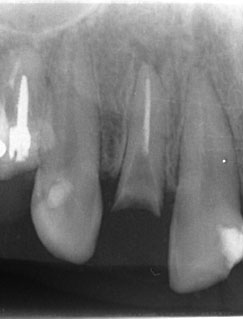

左上2は広範囲にわたってCRが充填されているのがわかります。またその周囲に透過像があり、カリエスになっていることもわかります。

| 根の中の薬が十分に充填されておらず、根の先が周りと比べて黒くなっており、炎症があると判断できます。 | 根の中にしっかりとお薬を緊密に充填しましたが、まだ根の先に黒くなっている部分があります。 |